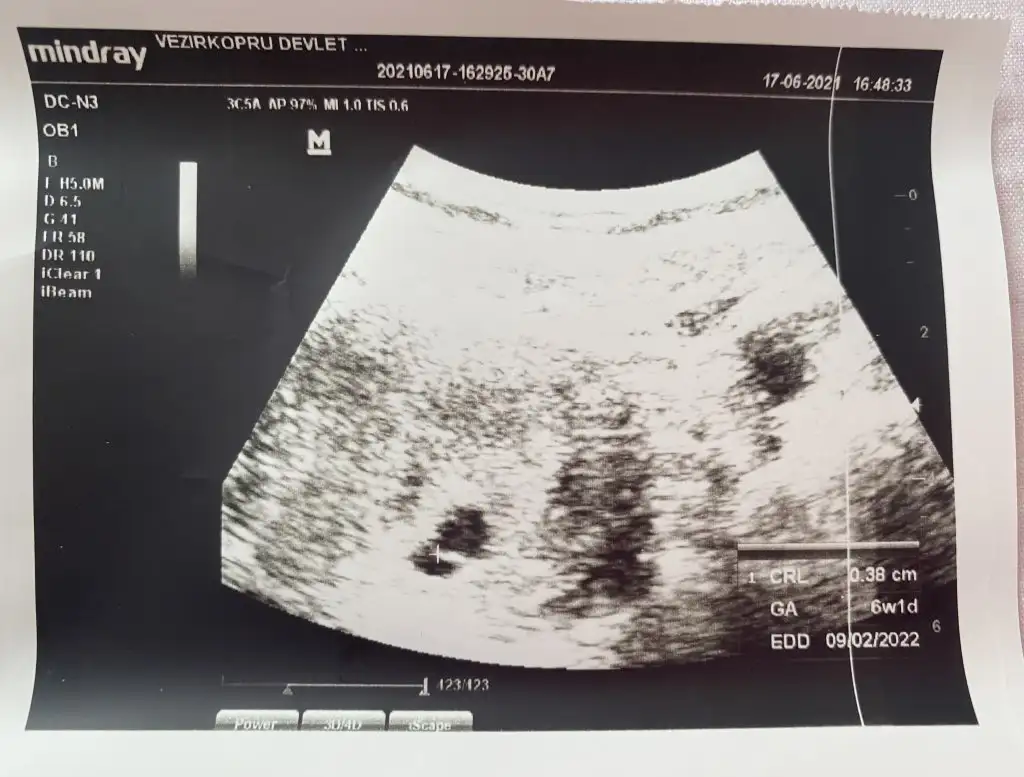

Merhaba ben 15 Nisanda kürtaj oldum.Adet olmadan kürtajdan 40 gün sonra hamile olduğumu öğrendim 25 Mayısta kese karından görünmedi alttan bakınca doktor yeni oluşan bi kese olduğunu düşündü 28 mayısta karından keseyi gördü.Keseye göre 5 hafta dedi.(5 hafta olma imkanı yoktu ama adet tarihine göre hesaplamadan dolayı 2 hafta fazla gibi hesaplandığından galiba ) 2 hafta sonra gel kalbine bakalım dedi.İlk hamileliğimde 6+2 de bebeğin kalbi durmuştu bende dayanamadım 11 gün sonra (8 Haziranda) 6+4 olması gereken zamanda özele gittim. Doktor henüz kesenin küçük olduğunu 20 mm olduğunda kalp atışının duyulduğunu söyledi.Keseye göre 6+3 tü bir güne takılmadım cihazdan da farkedebilir.Bebek çok küçük bir nokta şeklindeydi tutunmuş dedi. 2-3 hafta sonra gel dedi kalp için. 1 hafta geçtikten sonra ben devlete gittim. Kendi göründüğüm doktorun işi çıkmış gitmiş. Başka bir doktora göründüm ama o doktora hiç güvenmiyorum baktı daha kalp atışı yok 2 hafta sonra gel dedi kaç haftalık göründüğünü sordum 5+6 dedi (normalde 7. Haftada olması lazım) durumu anlattım bir hafta öncesinde 6+3 dendiğini doktor benim cihazımda ben bu şekilde ölçtüm 2 hafta sonra gel demekten başka bir şey söylemedi. Tabi haftasını o şekilde söyleyince ben kafamda bitirdim yine kalbi durdu diye düşündüm.O günden sonra kahverengi lekelenme başladı akıntının içinde kan görünce ben bebeği düşüreceğimi düşündüm korktum. Devletteki diğer doktor gelmişti ona gittim durumu anlattım baktı kese düzgün görünüyor dedi. Özelde çok küçük bi noktada olan bebek daha belirgin görünüyordu bu sefer Keseye göre değil de bebeğe göre ölçtü 6+1 çıktı 2 gün önceki ile de uyumluydu ama önceki haftalarla uyumlu değil. Kalp atışı yine yoktu.Kendimce düşünüyorum diğerlerinde Keseye göre ölçülmüştü şimdi bebeğe göre ölçüldüğü için mi acaba diyorum ama kese 8 haziranda da 17 haziranda da 13 mm idi. Kese gelişmeden bebek gelişir mi anlamadım. Doktor progestan verdi 1 hafta sonra gel dedi dinlenmemi bol su içmemi ilişkiye girmememi söyledi. Progestanı kullanıyorum ama acaba ölü bebeği mi karnımda tutuyorum ilaç kullanarak diye düşünüyorum.Güvenmediğim doktor hariç ultrason görüntülerini vermişti aşağıya ekledim birisi hariç diğerleri devlet. Bu konuda bilgisi olan benzer durum yaşayan yardımcı olur musunuzBen zaten kötüyü kabullendim gerçek neyse onu öğrenmek istiyorum